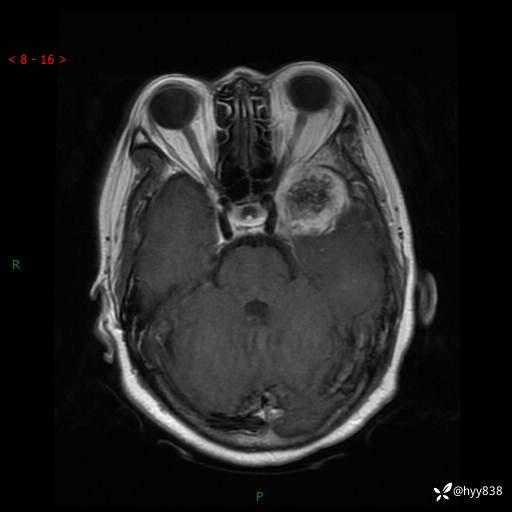

现病史:患者于1个月前无明显诱因出现左眼视力下降,无头痛,无恶心、呕吐,无肢体活动障碍,无意识障碍等伴随症状,后就诊于监利市人民医院行眼眶MRI检查提示“左侧中颅窝底占位性病变”,今日为求进一步诊治前来我院,门诊以“颅内占位性病变”收入院。 发病以来,患者精神、饮食及睡眠良好,大、小便正常。

颅脑MRI平扫+增强